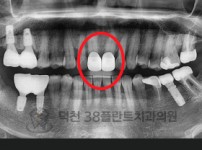

치료전후